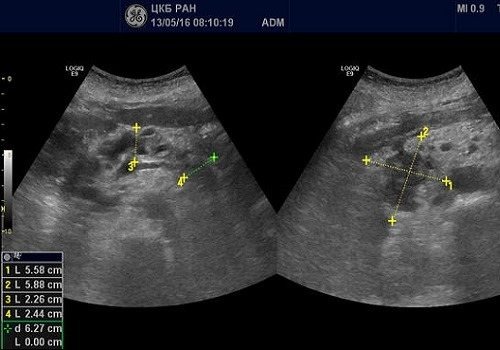

С помощью методов визуализации определяют место расположения, размер, плотность опухоли, метастазы, вовлечение в процесс лимфоузлов, сосудов, соседних органов.

Рак на УЗИ выглядит в виде объёмного образования в структуре органа. Оно может выявиться в зоне головки, тела или хвоста. На УЗИ визуализируется размер, форма и плотность опухоли. При раке головки отмечают её увеличение. Она приобретает округлую форму. Выявляют распространение злокачественного процесса на соседние органы, прорастание опухоли в близлежащие сосуды, появление метастатических очагов в лимфатических узлах.

Опухоль на мониторе аппарата УЗИ просматривается в качестве объемного новообразования, имеющая неправильную форму и неровные края. Наблюдается изменение тканей поджелудочной железы низкой эхогенности. Образование неоднородной структуры. Нередко возникают сложности дифференциации образования от псевдотуморозной формы панкреатита, потому требуется тщательное исследование панкреатического канала. При болезни основной панкреатический проток выглядит расширенным, на своем протяжении его диаметр неравномерный. Когда есть рак, канал расширяется только ниже опухоли.

При проведении УЗИ можно увидеть характерный эхопризнак ракового новообразования — значительное увеличение отдельной части железы или выбухание ее контура. В 50-80% случаев в онкозаболевание вовлекается головка ПЖ. Даже опухоль незначительных размеров является хорошо видимой в головном конце на УЗИ. Это связано со следующими причинами:

При раке ПЖ изменяются контуры органа: они становятся нечеткими, но, в отличие от хронического панкреатита, не имеют неровностей или зазубрин. В месте расположения опухоли визуализируются выпуклости, которые проникают в окружающую клетчатку в виде языков. Все это подробно описывается в заключении УЗИ.

При наличии опухоли в головке ПЖ анализируются данные расширенного вирсунгова протока: при раке выявляются ровные и неуплотненные стенки, в отличие от их изменений при хроническом панкреатите. Если диаметр главного выводного протока равен примерно половине толщины самой ПЖ, это является одним из признаков злокачественного процесса.

На УЗИ можно диагностировать сдавление и смещение проходящих рядом сосудов – нижней полой и брыжеечной вены. Это наблюдается и при хроническом панкреатите, и при опухоли, но в случае злокачественного образования выражено значительнее. При локализации опухоли в головной части ПЖ происходит смещение верхней брыжеечной вены в вентральном направлении, а при достижении узлом больших размеров сдвигается и сама головка.